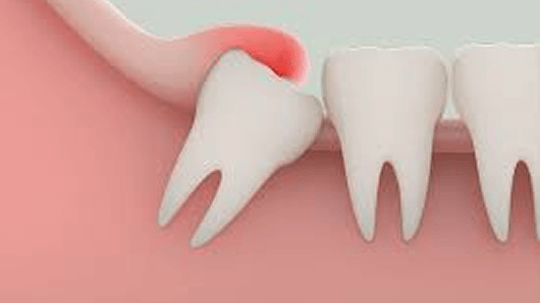

橫生智慧齒

並非所有智慧齒都需要拔除,但若出現以下情況,建議及早處理: